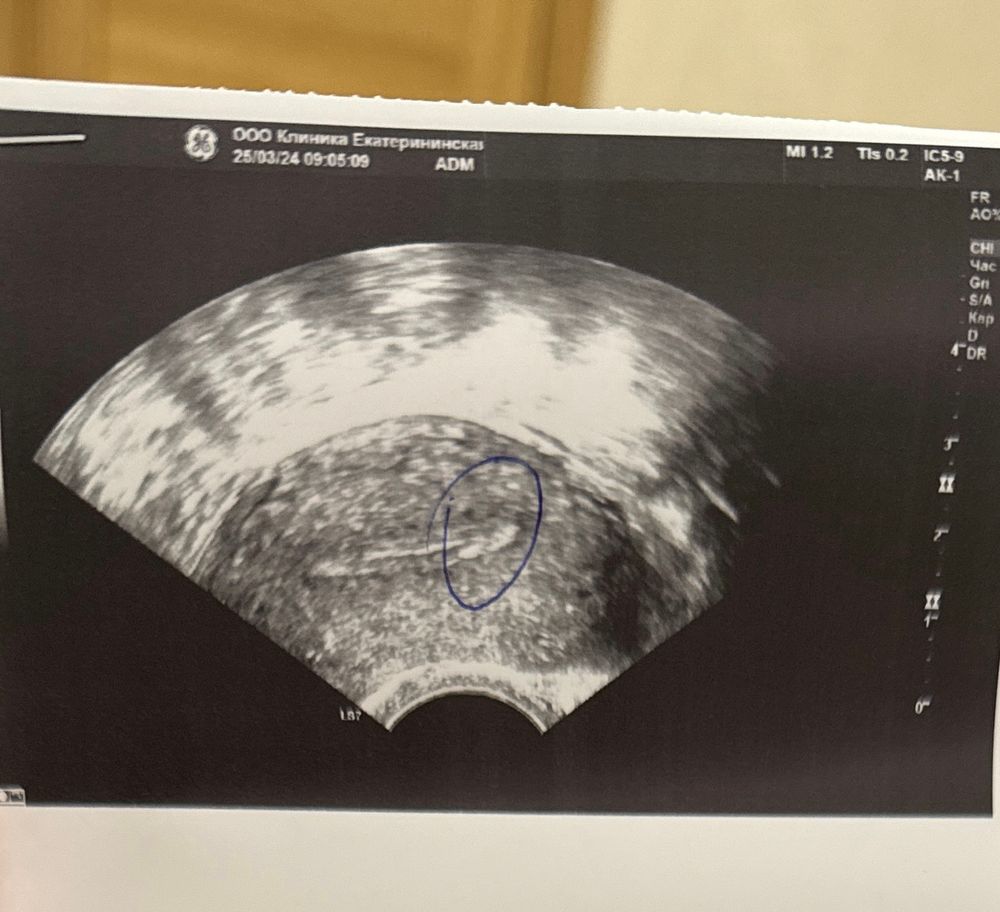

Плохо растет эндометрий

Митральный двухстворчатый